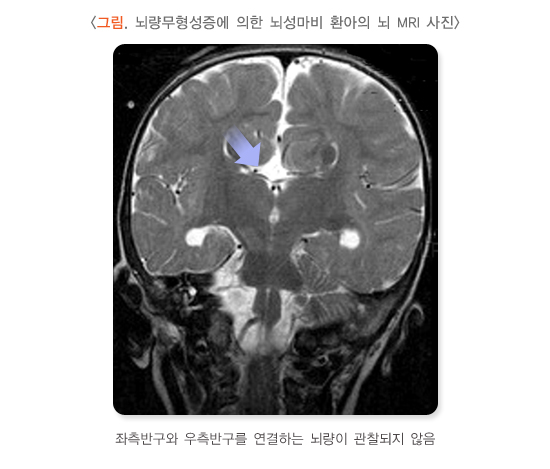

1. 선천성 뇌기형

임신 초기와 중기에 태아의 신경세포들은 빨리 증식해 주로 뇌의 내측에 존재하다가, 나중에 특정 위치로 이동(이주)해 특별한 기능을 수행합니다. 임신 초기에 뇌가 정상적으로 발달하지 않아 신경세포가 제대로 이동하지 못하면 선천성 뇌기형이 발생할 수 있습니다. 정상 인구에서 1,000명 중 약 3명이 선천성 뇌기형을 갖고 있는 반면, 뇌성마비에서는 약 10명 중 1명에서 선천성 뇌기형이 관찰됩니다. 뇌기형의 원인은 대부분 알 수 없지만 유전질환, 염색체 이상, 혈액 공급 장애 등이 관련된다고 추정합니다.